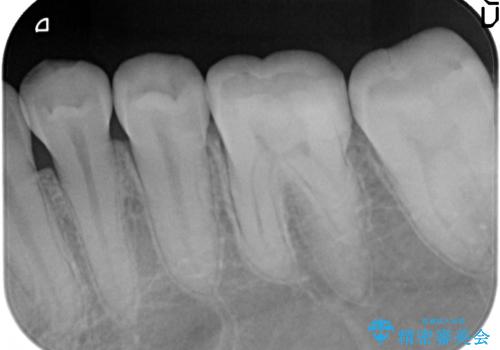

- 冷たいものを飲むと、左下奥歯がしみると来院された方の症例です。

検査の結果左下6が虫歯になっていたため、セラミックインレーによる修復を行いました。